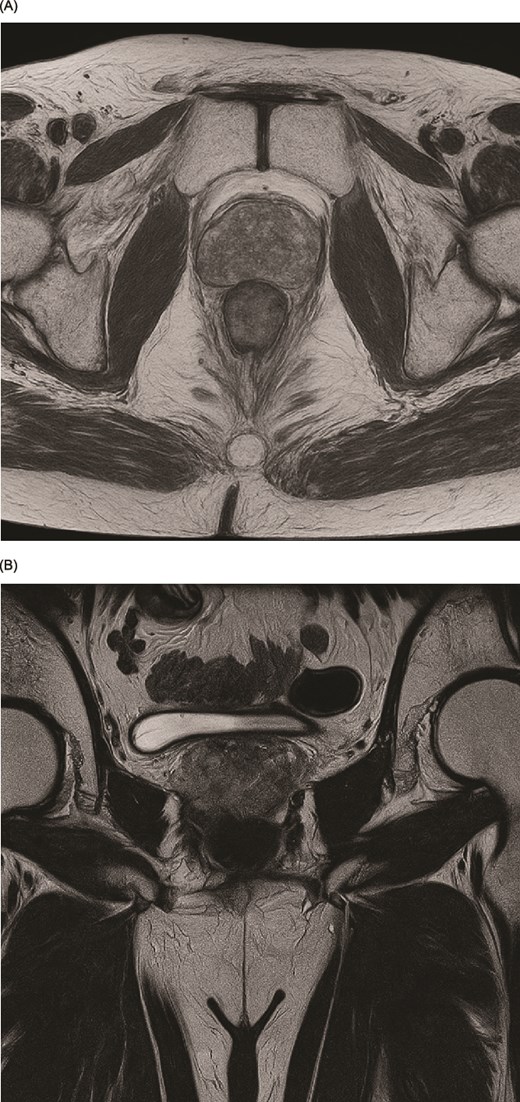

Multi-parametric magnetic resonance imaging (MRI) of his prostate (Fig. 1A and B) demonstrated two lesions (PIRAD 4&5). The prostate volume measured 32.83 cc, giving a PSA density of 0.23 ng/ml2. No pelvic or para-aortic lymphadenopathy identified and no MRI signal abnormality of the bone marrow. His preliminary MRI staging was T3a N0 M0.

(A, B) Preoperative magnetic resonance imaging (MRI) of the prostate in T2-weighted sequence demonstrating the lesion. (A) Axial view. (B) Coronal view.